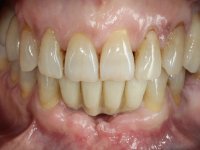

Após estudo imagiológico foi planificada a colocação de dois implantes de 3.3 mm de diâmetro e 10 mm de comprimento. No dia da cirurgia foram extraídos os dentes 42 e 32 e removido o implante. Os implantes foram colocados na zona dos alvéolos tendo o cuidado de lingualizar um pouco o seu posicionamento. Foi feita uma impressão pela técnica de moldeira aberta com o retalho aberto para a confeção da ponte provisória imediata. Enquanto a impressão foi para o laboratório, foram colocados parafusos de cicatrização altos e feita a sutura da ferida cirúrgica. A paciente esperou 2 horas na sala de espera enquanto no laboratório era confecionada a ponte provisória. A ponte provisória imediata aparafusada foi colocada e o seu assentamento controlado imagiologicmente. Passados 3 meses foi realizada a impressão definitiva com uma técnica de moldeira aberta. Nessa consulta aproveitamos para polir a ponte provisória com taças de borracha para que os tecidos moles pudessem maturar em melhores condições. Foi feita a recolha de informação para caracterizar da melhor forma a estrutura monolítica em Zr. Foram utilizadas guias de cor para a cerâmica de tonalidade coronária e gengival. No laboratório foi confecionada uma ponte em Zr. aparafusada que foi cuidadosamente caracterizada. Após aprovação pela paciente foi colocada definitivamente em boca. O aperto foi feito com uma chave dinâmica com 35 N de torque. Os orifícios foram tapados com teflon e obturados com resina composta.